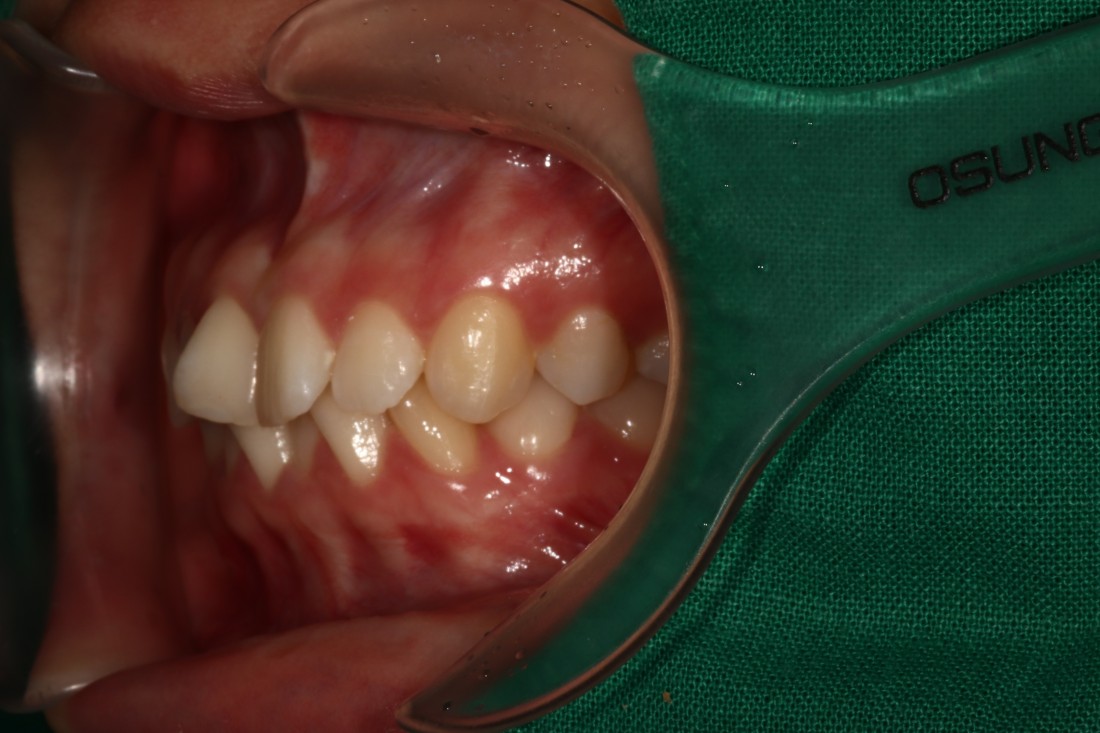

광주 교정치과는

200케이스 넘는 교정사례를

상세하게 공유해드리고 있기 때문에

실력을 믿고 맡기셔도 좋습니다.

더 다양한 교정 전/후 사례는

위의 사진을 클릭하시면

확인하실 수 있습니다.